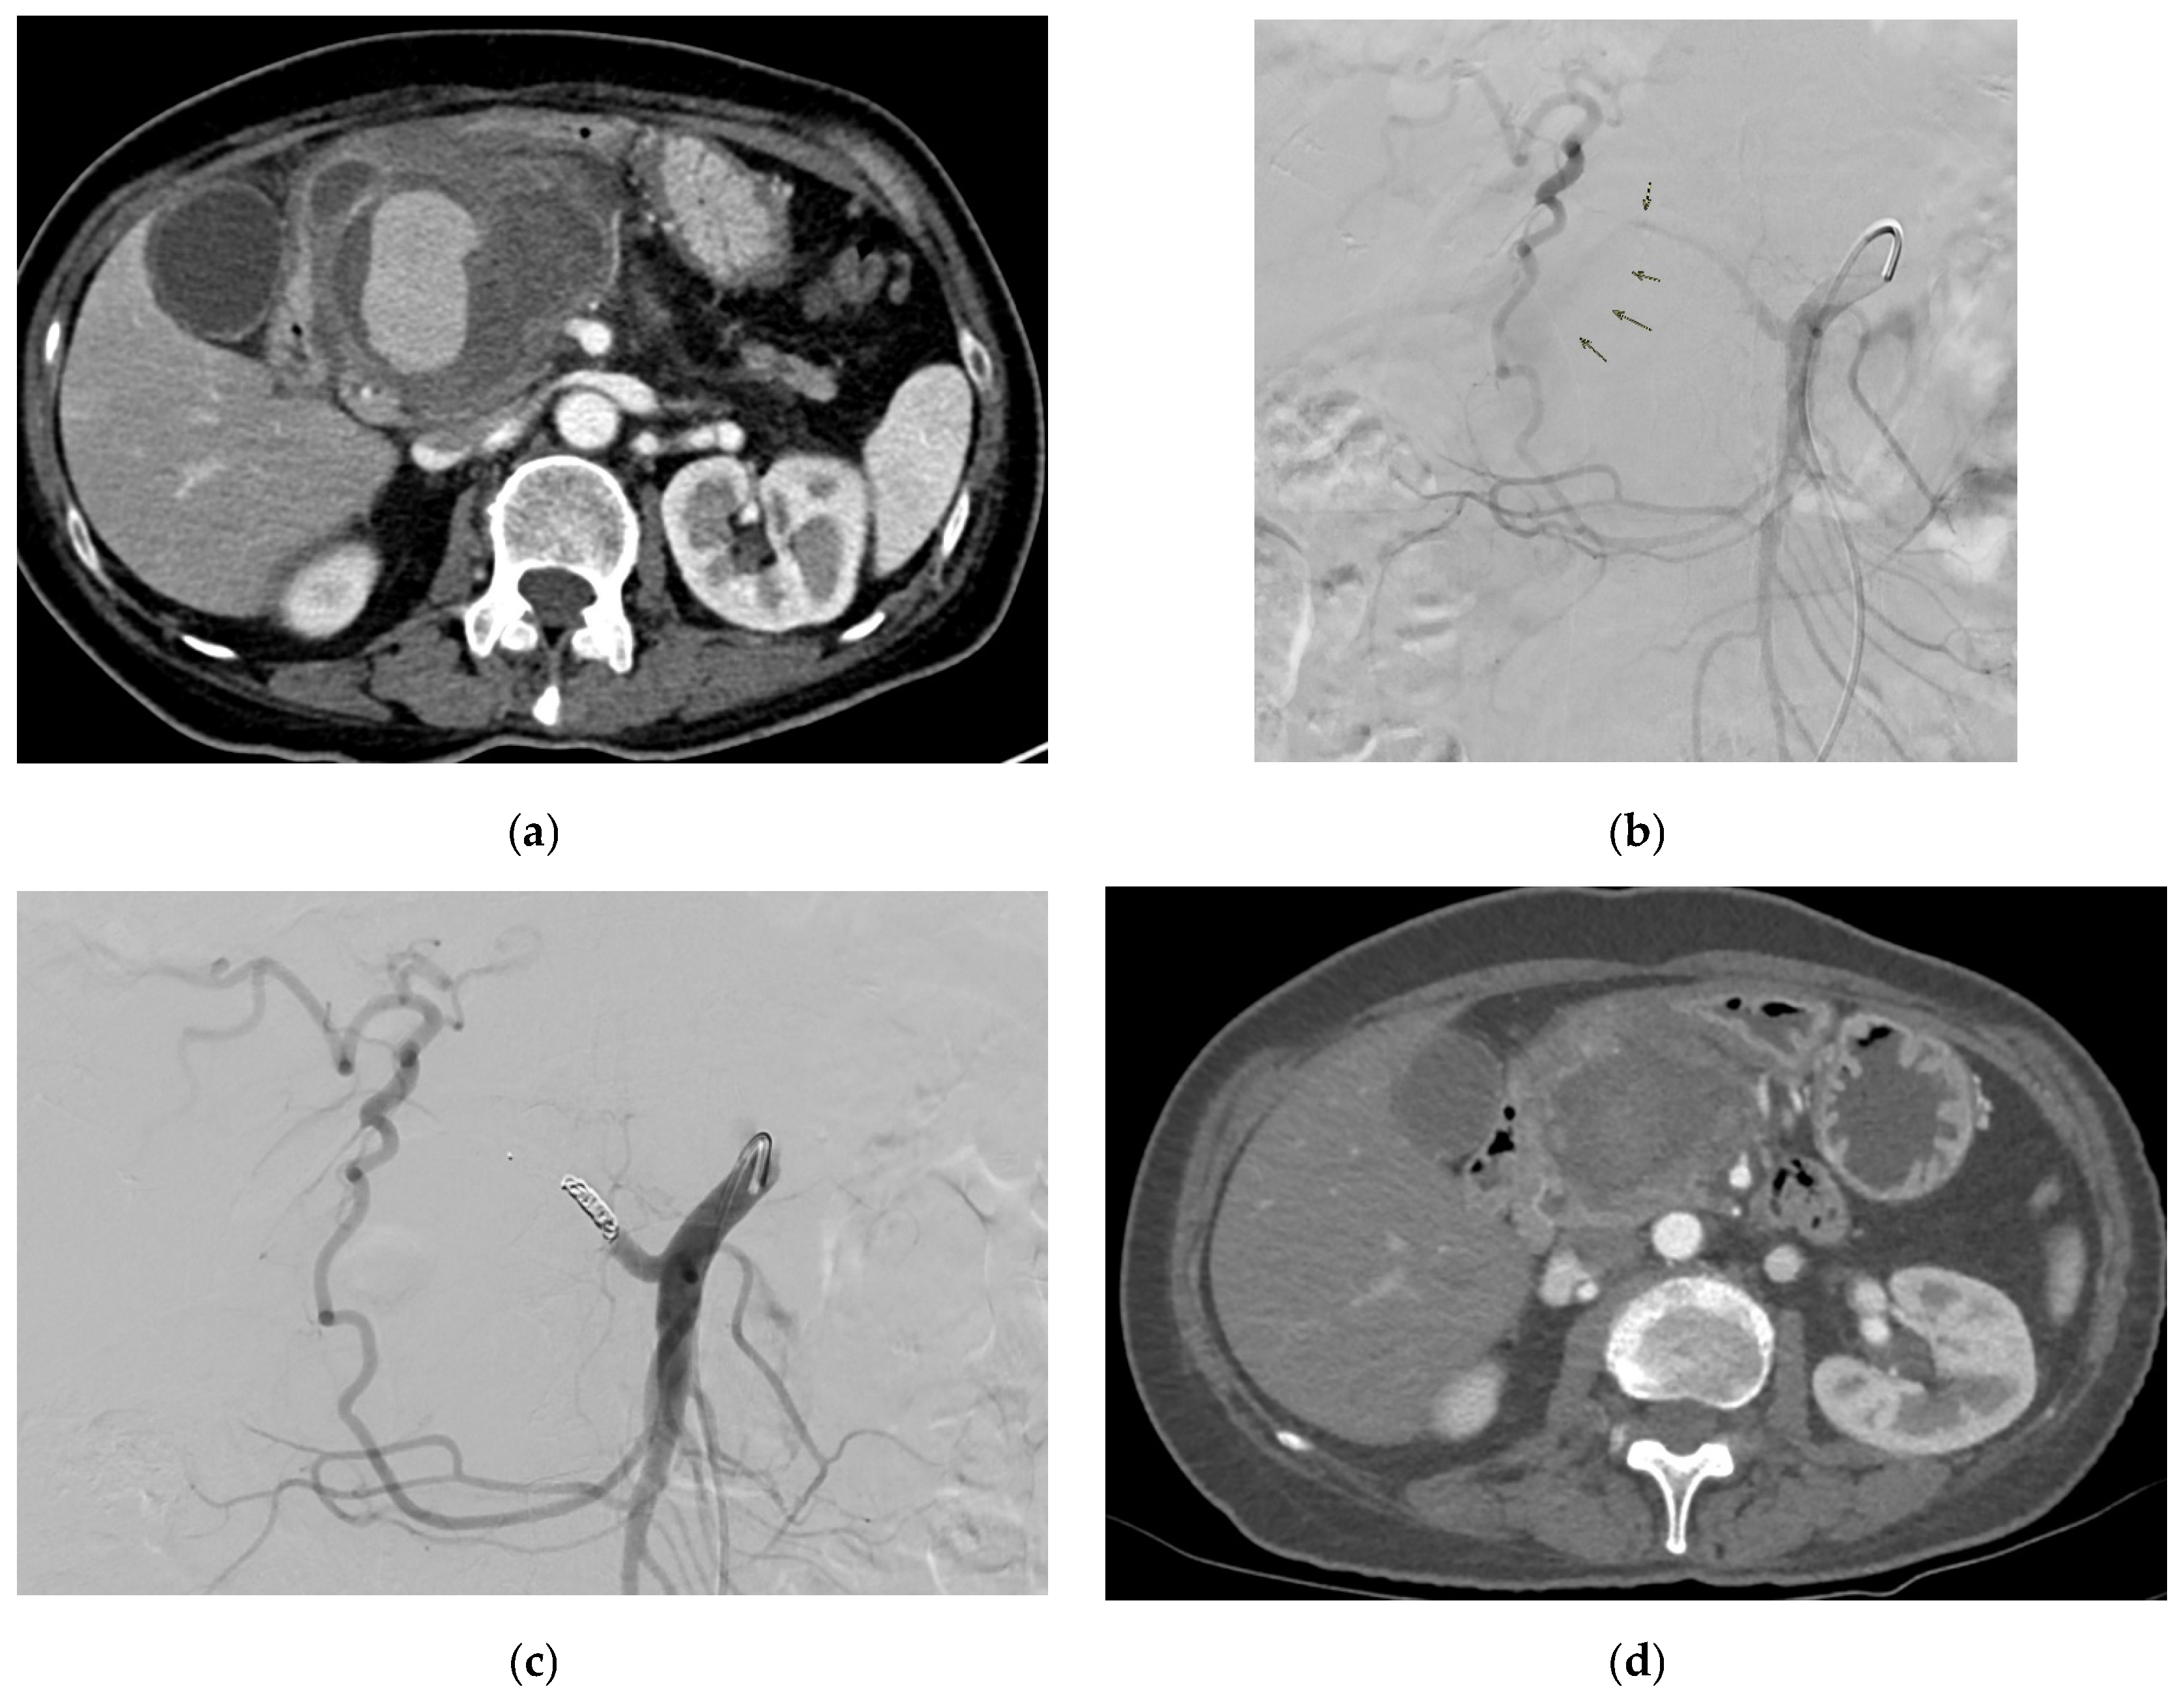

- Madhusudhan, K.S.; Gamanagatti, S.; Gupta, A.K. Endovascular embolization of pseudoaneurysm of left colic artery developing after renal biopsy. Indian J. Nephrol. 2015, 25, 242–245. [Google Scholar] [CrossRef] [PubMed]